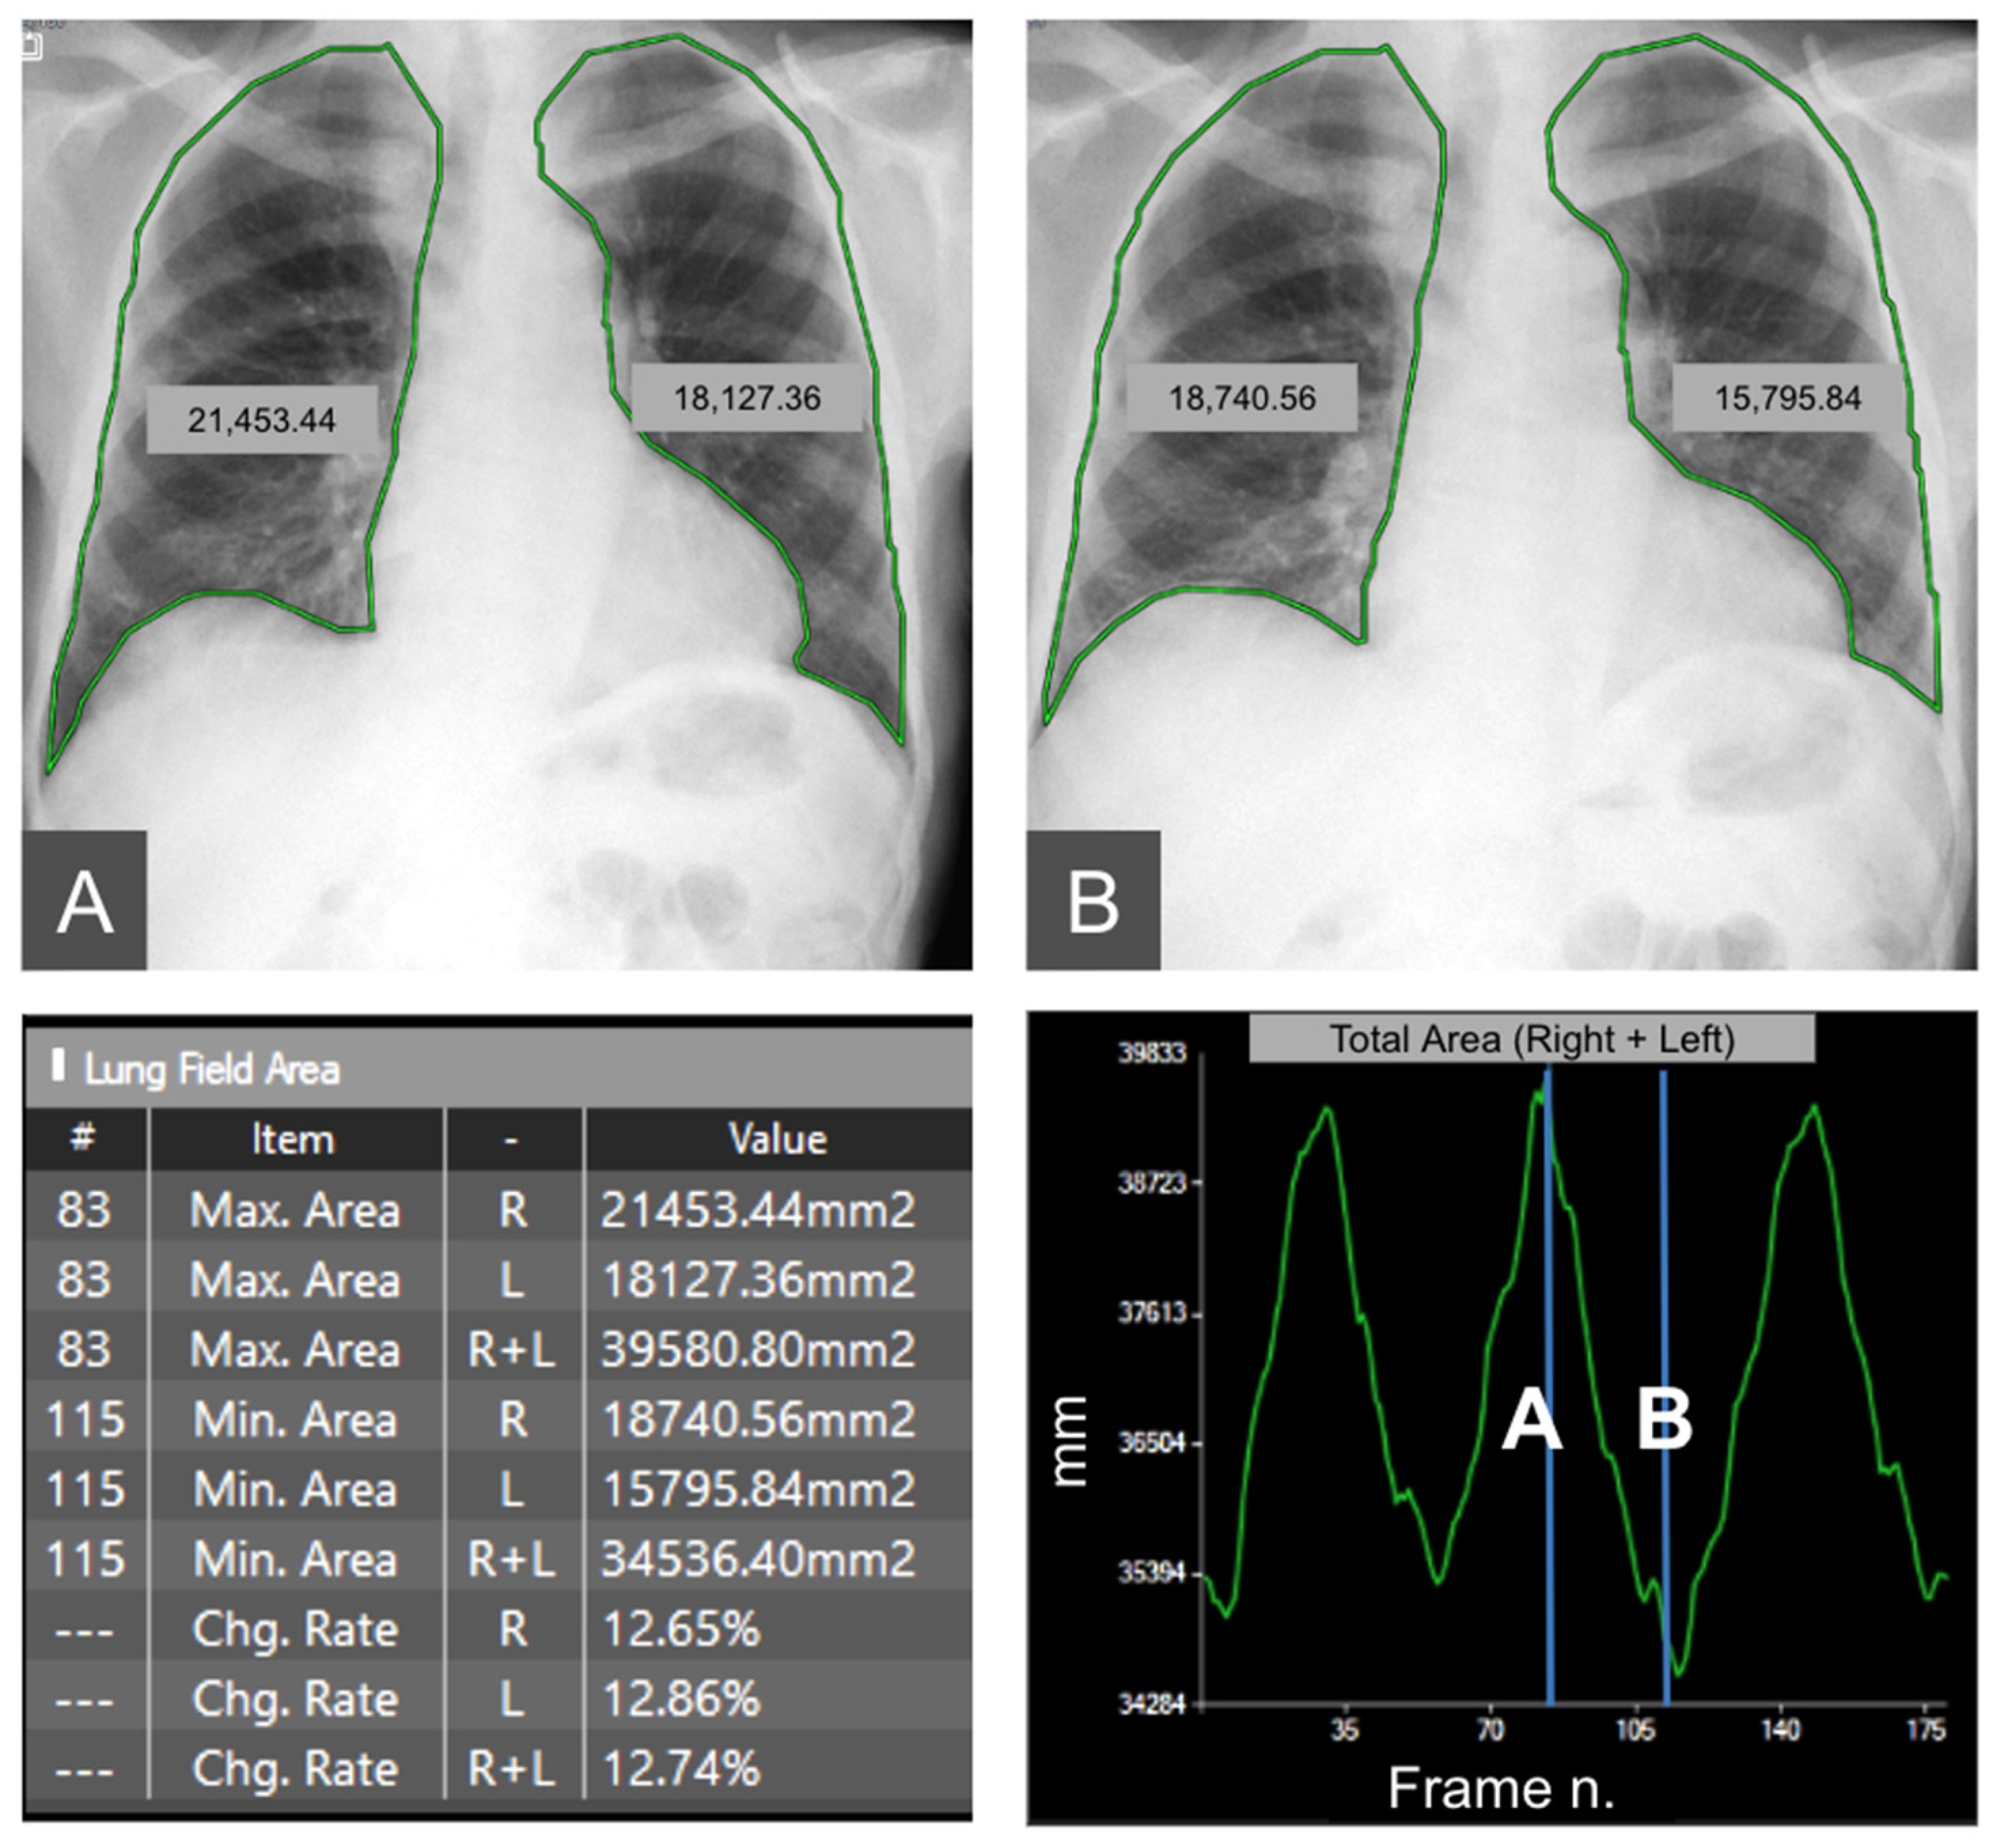

| DM-mode | Tracking diaphragm motion. Automatic calculation of the lung area and the relative changing rate (%). | Tracking of diaphragmatic domes represented in a motion–time graph. Area detection through an edge detection method in the post processing phase. | Diagnosis of diaphragm motion impairment and palsy. Automatic calculation of the respiratory rate. Analysis of lung dynamics in patients with restrictive/obstructive diseases. Follow-up of patients in pulmonary rehabilitation. |